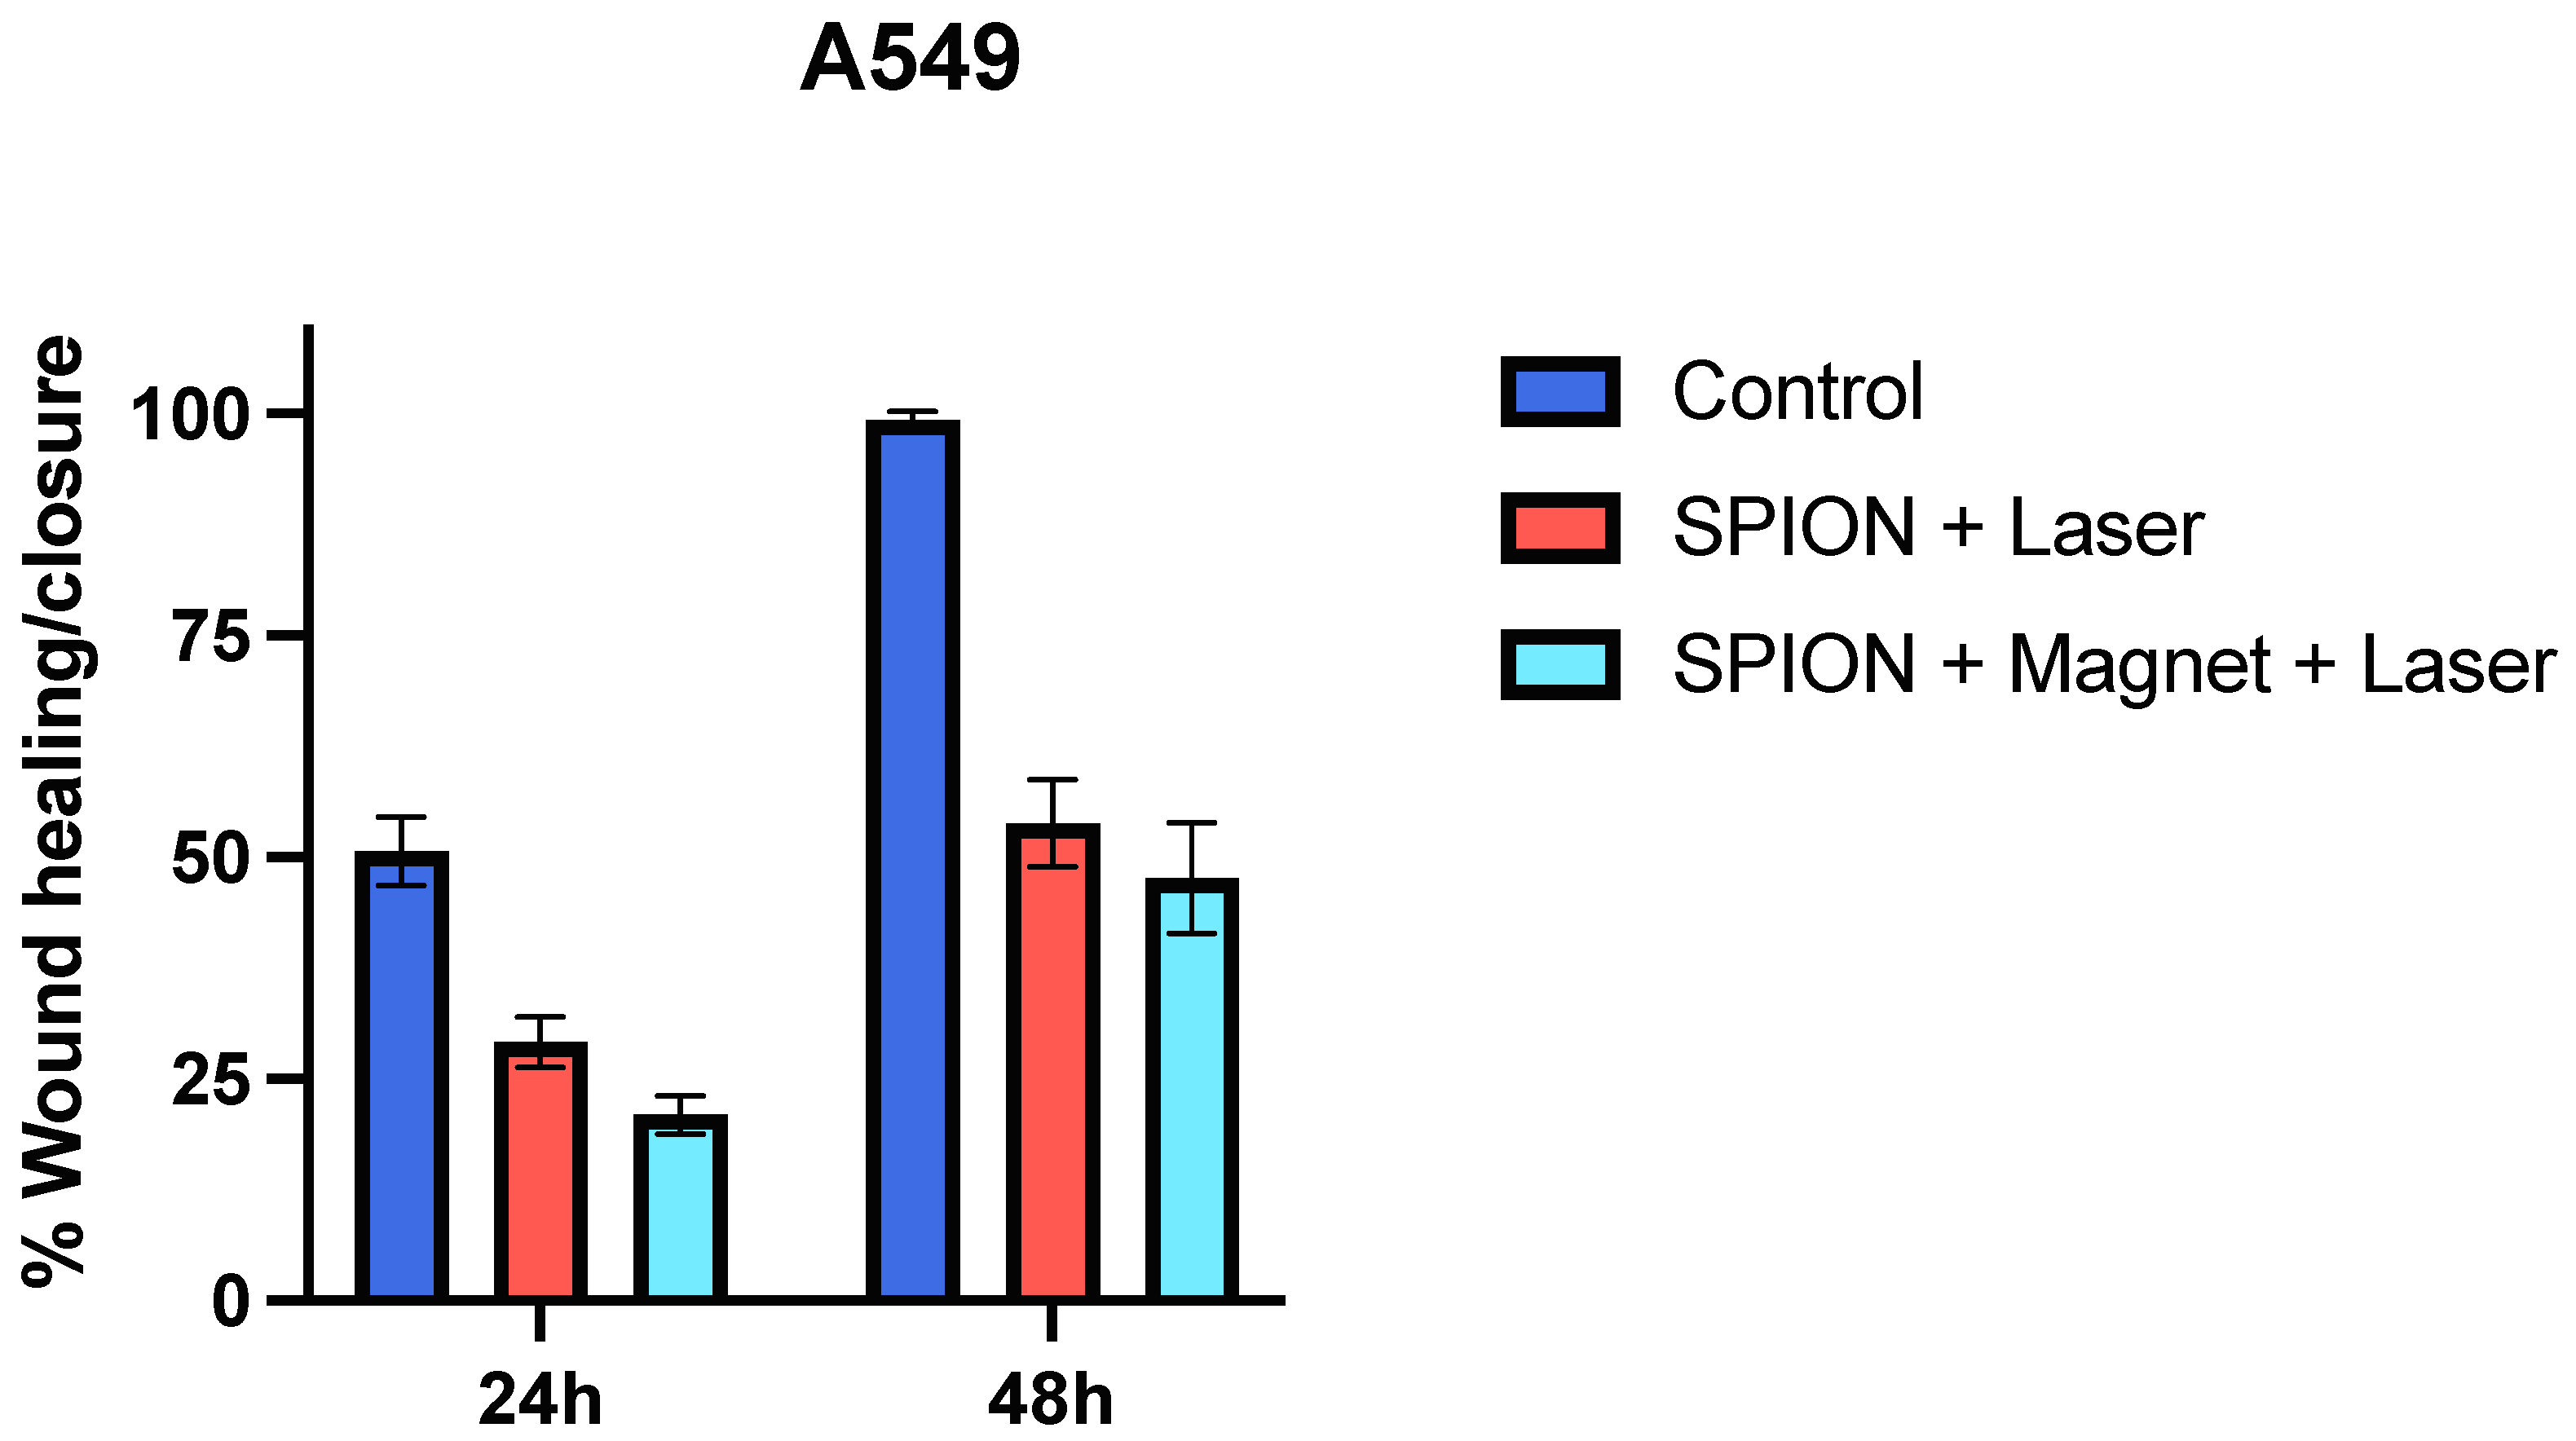

2.8.3. Wound Healing/Scratch Assay